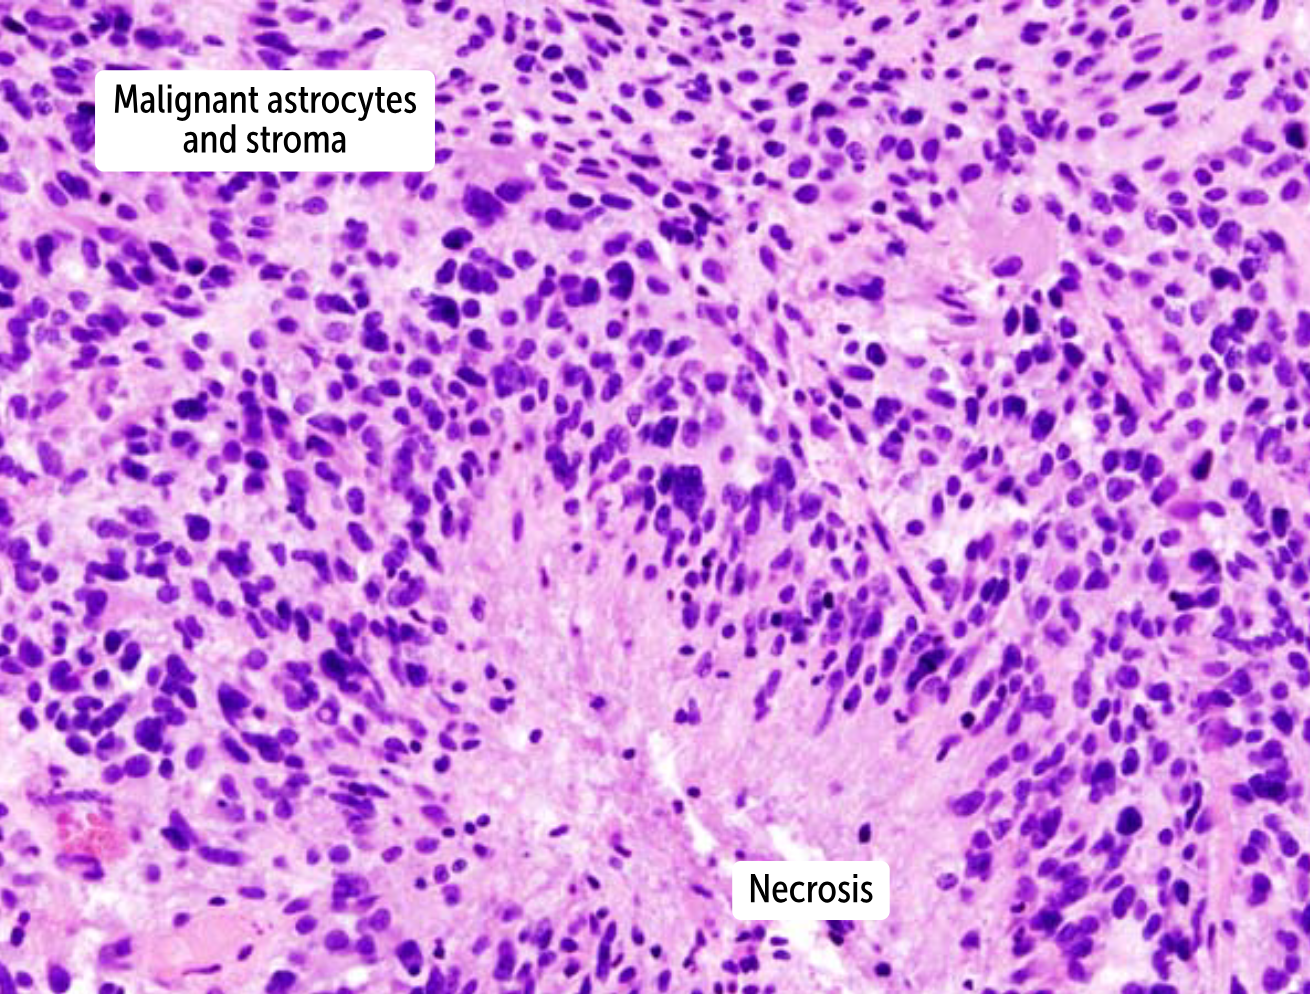

Histologic features of

Glioblastoma

A

Hypercellular

nuclear atypic

mitotic acitivity

GFAP+ [13f]

pseudo palisading necrosis [13e] sash

microvascular proliferation [13c] red hair beard moustache